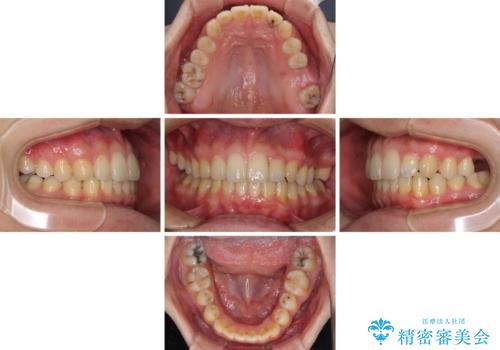

- 前歯のクロスバイトと、大学生のころから放置している虫歯を気にして来院された患者様です。

マウスピースでの矯正治療を希望されていましたが、前歯のクロスバイトは不十分な仕上がりや歯髄壊死などのリスクが高くなるため、術前にワイヤーで大まかに整えてからインビザラインにて矯正治療を行うこととしました。

奥歯の虫歯は抜歯が必要であったので、矯正治療前に抜歯をし、矯正治療と並行してインプラントによる補綴治療を行うこととしました。